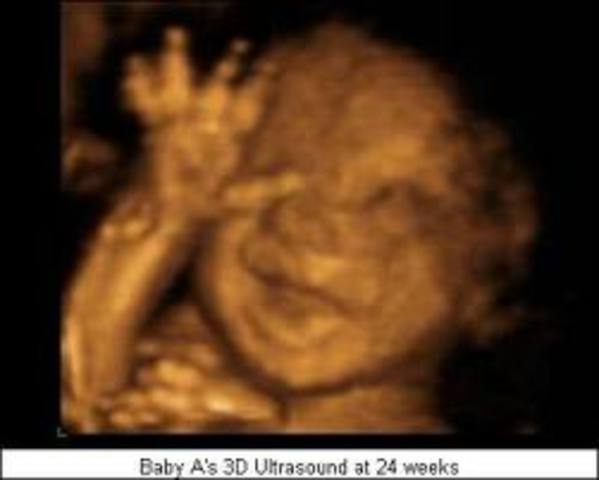

The size of th.e baby is now 10-12 inches long and weighs about 1 and 1/2 lbs.

Periods of activity followed by periods of rest and quiet.